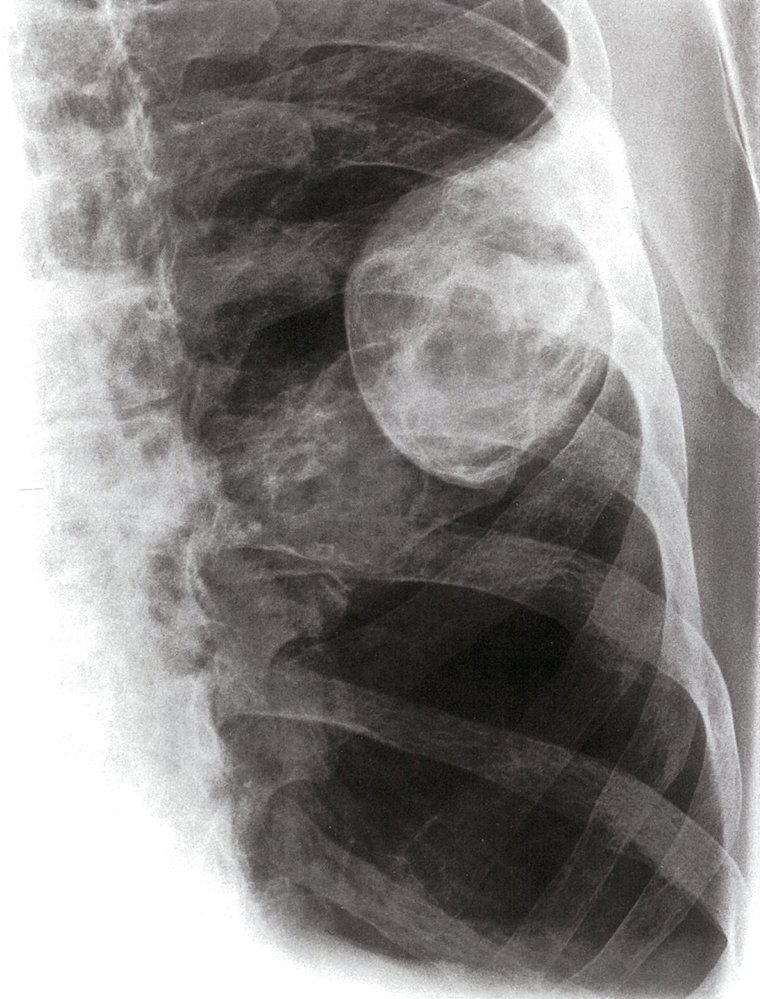

Aneurysmal bone cyst

• Mostly septated, blood-filled cysts

• Peak incidence: 10–20 years

• May affect any bone

• Most common localizations: spine and metaphysis of the long bones

• Predominantly affects the lower extremities

• Local pain and swelling may occur.

• X-ray: osteolytic lesion with definite margins; usually located in the metaphysis

• MRI: multichambered lesion with fluid-fluid levels

• High risk of recurrence

• Description

• Osteolytic lesions; usually septated, blood-filled cysts

• Idiopathic (primary aneurysmal bone cyst) or secondary to malignant or other benign bone diseases (secondary aneurysmal bone cyst)

• Epidemiology: peak incidence between 10 and 20 years

• Clinical features

• Common sites are the spine and the metaphysis of the femur and tibia.

• Usually asymptomatic; local pain and swelling may occur

• Pathological fracture: often the first sign

• Diagnostics

• X-ray: metaphyseal, osteolytic lesion with sclerotic margins

• MRI : septated, blood-filled lesions, with typical fluid-fluid levels.

• Treatment: surgical curettage and bone grafting

• Prognosis: high risk of recurrence